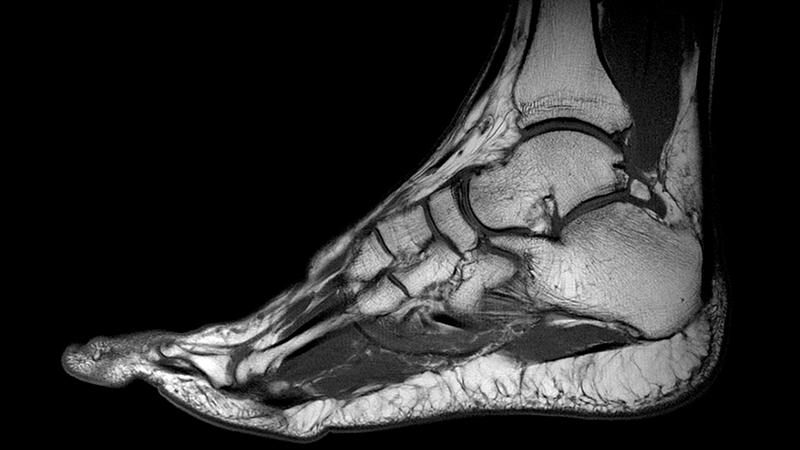

Врачи подчеркивают важность понимания анатомии голеностопного сустава для диагностики и лечения травм и заболеваний. Этот сустав, состоящий из большеберцовой, малоберцовой костей и таранной кости, обеспечивает стабильность и подвижность нижней конечности. Специалисты отмечают, что сложная структура связок и сухожилий, окружающих сустав, играет ключевую роль в его функциональности. Понимание анатомии позволяет врачам более точно оценивать механизмы травм, такие как растяжения или вывихи. Кроме того, знание анатомических особенностей помогает в разработке эффективных реабилитационных программ, что особенно важно для спортсменов и людей, ведущих активный образ жизни. Врачи рекомендуют регулярные обследования и внимание к сигналам организма, чтобы предотвратить серьезные проблемы с голеностопным суставом.

Голеностопный сустав состоит из двух основных костей: малоберцовой и большеберцовой. К ним снизу присоединяется таранная кость, а под ней располагается пяточная кость. В результате образуется структура, напоминающая блок, которая является характерной формой голеностопного сустава. В этой конструкции выделяются ключевые элементы: наружная (внешняя) и внутренняя лодыжки, а также дистальная часть большеберцовой кости.

Голеностопный сустав находится на стыке малой и большой берцовых костей с пяточной костью, которая является частью стопы. Существует четыре области голеностопа: задняя, передняя, наружная и внутренняя. Последние две расположены в области лодыжек. Передняя часть представляет собой тыл стопы, а задняя – область ахиллова сухожилия.